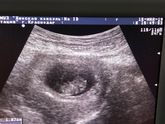

Вчера было ровно 11.Исчезло плохое самочувствие,грудь перестала болеть,вообщем исчезли все признаки,которые мучали меня до этого дня,даже живот сдулся(вздутие было)?.29 мая 1й скриннинг.Жду с нетерпением,чтобы убедиться,что с малышом всё в порядке,т … Читать далее